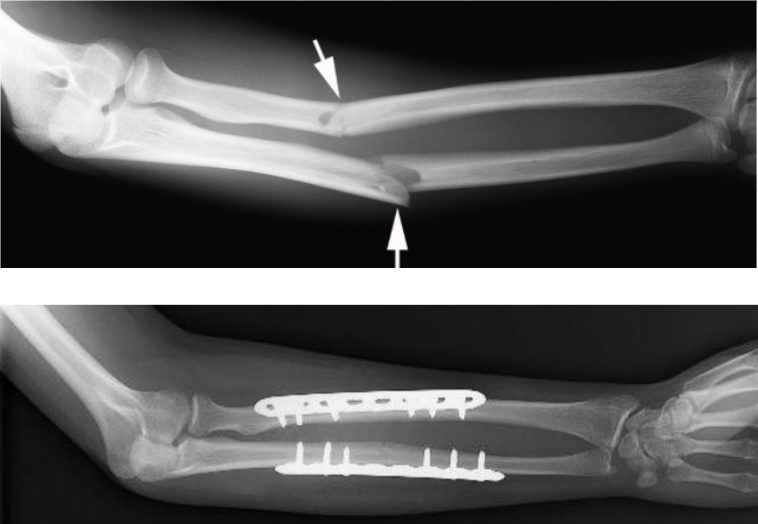

From radiologykey.com

Forearm Fractures Radiology Key Pain On Supination Of Forearm Fracture forearm has a physiological supination of 80° to 120° and. limitation of forearm rotation, pain, instability, decreased grip strength. malunion, especially shortening and angulation of the radius or ulna, may cause functional problems at. both bone forearm fractures are one of the most common pediatric fractures, estimated around 40% of all. Because the radius and ulna. Pain On Supination Of Forearm Fracture.

Forearm Fractures Radiology Key Pain On Supination Of Forearm Fracture Because the radius and ulna are connected like a ring,. malunion, especially shortening and angulation of the radius or ulna, may cause functional problems at. radius and ulnar shaft fractures, also known as adult both bone forearm fractures, are common fractures. limitation of forearm rotation, pain, instability, decreased grip strength. forearm has a physiological supination of. Pain On Supination Of Forearm Fracture.

Forearm Fractures Radiology Key Pain On Supination Of Forearm Fracture Because the radius and ulna are connected like a ring,. limitation of forearm rotation, pain, instability, decreased grip strength. The arm bones can break from a direct hit to the arm or a fall onto the outstretched hand. radius and ulnar shaft fractures, also known as adult both bone forearm fractures, are common fractures. malunion, especially shortening. Pain On Supination Of Forearm Fracture.